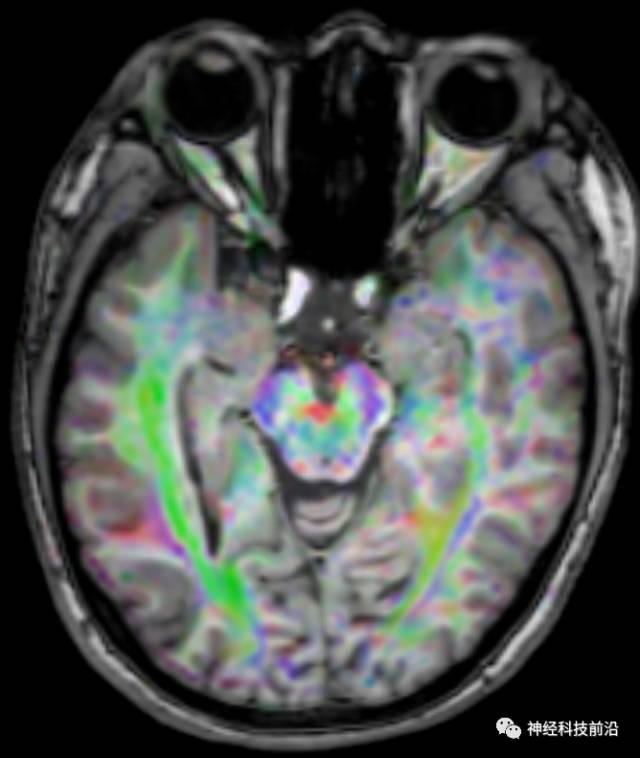

DTI原始图像

DTI原始图像与T1融合图像